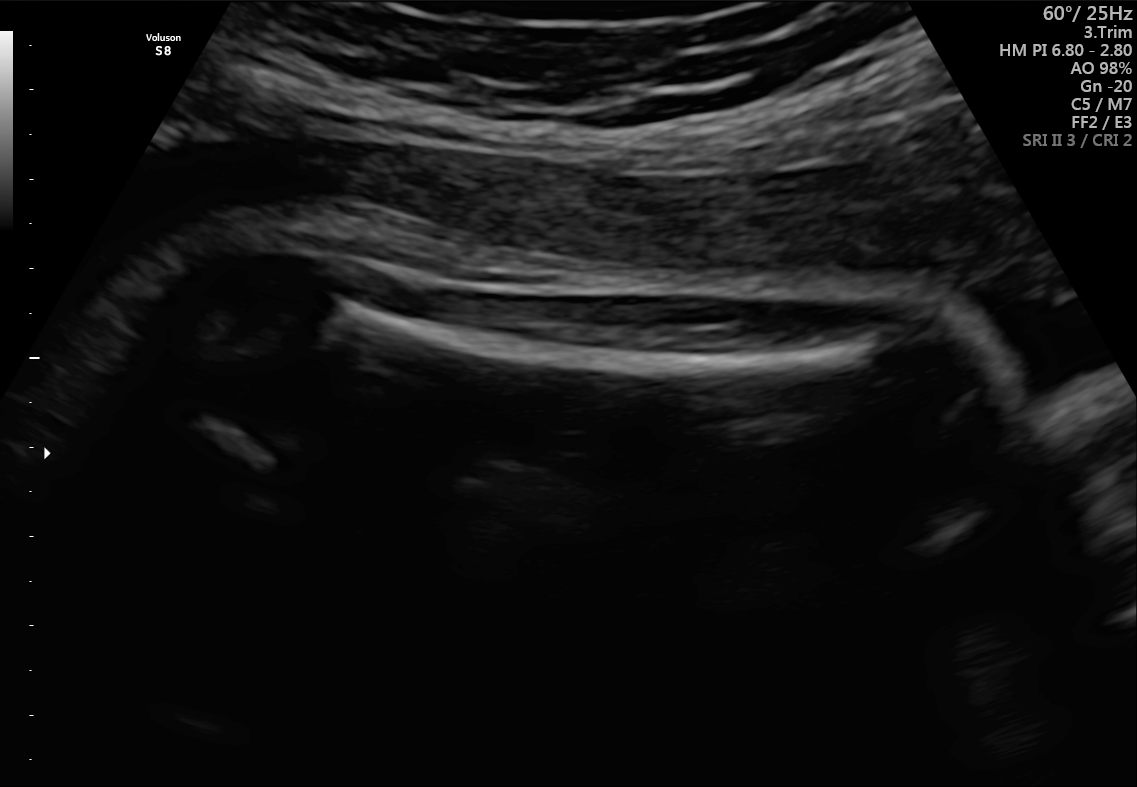

Refer to caption

(a) Fetal abdomen

(b) Fetal brain

(c) Fetal femur

(d) Fetal thorax

(e) Maternal cervix

(f) Other

Figure 1: Examples of real images in the FETAL_PLANES_DB dataset.

5.1 Visualization of Synthetic Images

The generated images were visually assessed by examining a sample of synthetic images from each of the six classes. The synthetic images were compared with the real images from the FETAL_PLANES_DB dataset in Figure 1 to evaluate their realism and similarity. Example images from the diffusion model are shown in Figure 2, where we observe that the synthetic images closely resemble the real images in terms of texture, structure, and class-specific features. This addition emphasizes the visual quality of the generated images, which was a key aspect of evaluating the success of diffusion models in this context.